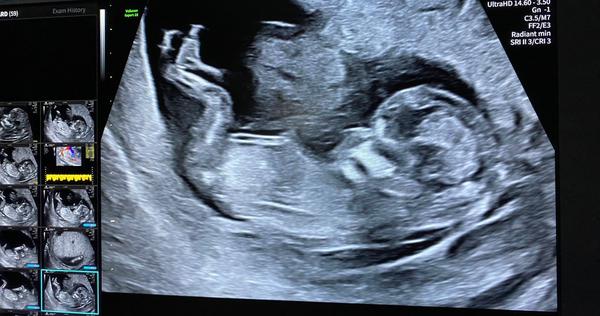

13. týden a pohlaví miminka. Je to chlapeček nebo holčička?

Krásný den, myslite, ze je to spis chlapeček nebo holčička?🙂 Dekuju🙂

Jestli to, co tam jde vidět je opravdu hrbolek, vypadá to podle úhlu n kluka. Ideální záběr to ale není. Zkus na FB nub theory.

Z ty fotky se to nepozná, vždyť tam není videt pohlavní hrbolek, je přes něj noha.

Jestli vidím správně, pohlavní hrbolek směřuje rovně, což by odpovídalo holčičce 😊